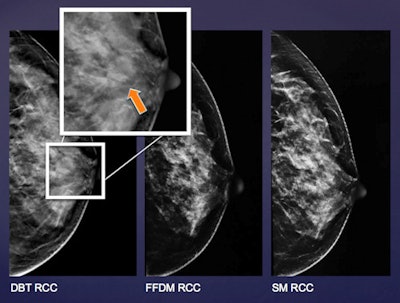

Researchers from Hong Kong have determined that digital breast tomosynthesis (DBT) had higher sensitivity and better characterized more lesions than full-field digital mammography (FFDM) and synthesized 2D mammography when screening women at moderate risk of breast cancer.

The ongoing, prospective study compared the lesion detection and characterization ability for both malignant and benign masses for FFDM, synthesized 2D mammography, and DBT. The researchers from Queen Mary Hospital also evaluated differences in radiologists' confidence levels when using the three modalities, finding DBT comes out on top with a sensitivity of 91.8%.

DBT has already proved its superiority to FFDM in multiple studies. Recent research has also focused on comparing FFDM to synthesized 2D mammography, in which synthesized 2D images are created from 3D datasets acquired with DBT. The hope is that synthesized 2D images could be used with DBT to eliminate the need for a 2D image acquired with conventional FFDM, thus lowering radiation dose.

Two-view FFDM and two-view DBT were performed in the same setting. Synthetic 2D mammograms were created from the DBT data. Nine radiologists reviewed the FFDM, DBT, and synthetic 2D mammography images without access to prior examinations or clinical history.

In terms of detecting benign or probably benign lesions, FFDM detected 102 lesions, synthetic 2D mammography detected 85, and DBT detected 125. For suspicious lesions, FFDM detected 11, synthetic 2D mammography detected 13, and DBT detected 15.

DBT also demonstrated sharply higher sensitivity than the other two modalities.

Sensitivity | 69.0% | 65.5% | 91.8% |

Specificity | 94.7% | 96.3% | 94.8% |

Positive predictive value | 64.5% | 67.9% | 68.3% |

Negative predictive value | 93.4% | 94.6% | 97.9% |